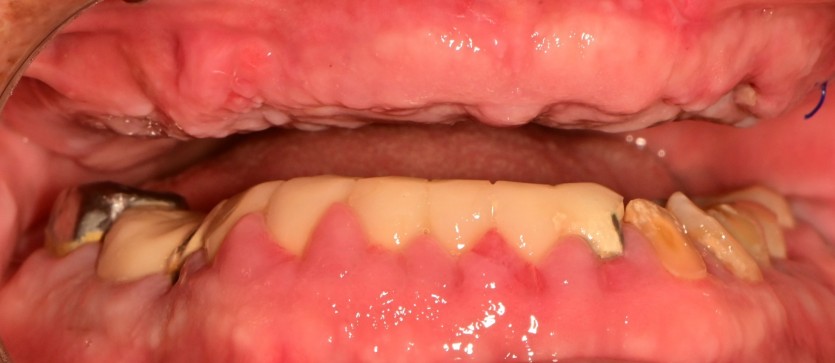

상악 전체 임플란트 증례입니다.

10개의 임플란트로 완성하였습니다.